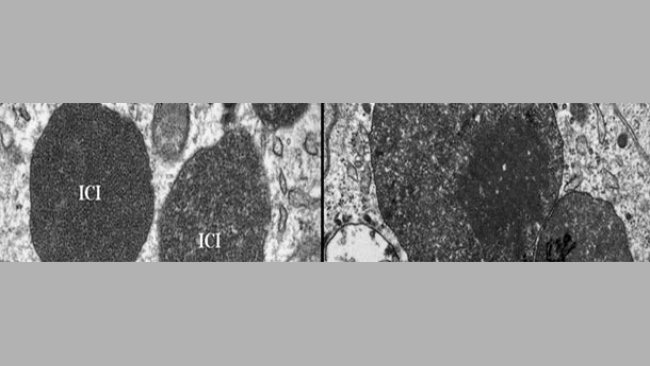

Novità sulle vie di eliminazione, vie di trasmissione, fattori di rischio e la spiegazione del perchè il PCV2 diventa patogeno.